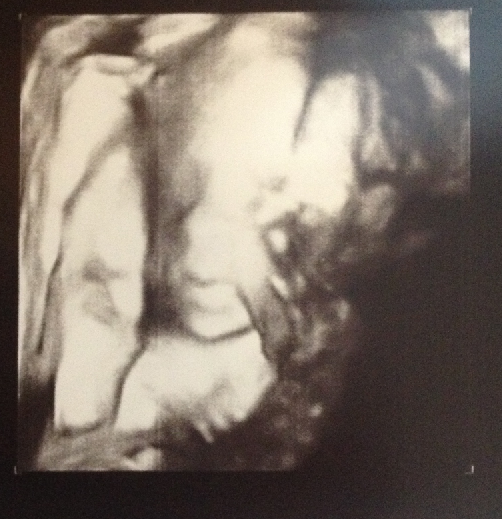

可是小寶貝有點不配合,

一直用手遮住臉

不過還來寶寶還是只有遮臉照...

這一張是比較清楚的唷

| 迪生一直說像他,,,,可是我覺得像我臉圓圓比較有福氣樣壓!!!! |